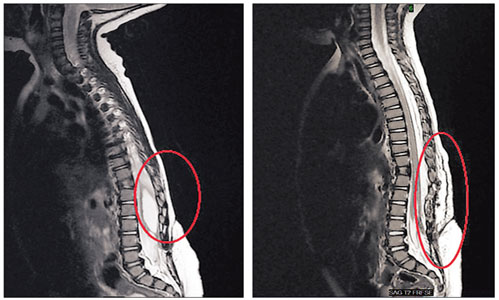

الرنين المغناطيسي أهم وسيلة لرؤية الانزلاق الغضروفي الأشعة التشخيصية